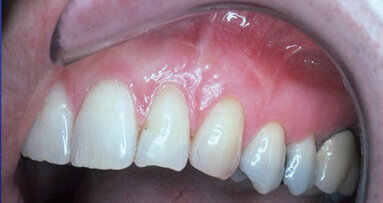

Case No. 1

The patient presented with an obvious singular defect of recession at the gingival area of tooth #11 (Fig. 1).

Using a collagen barrier with the coronal repositioned flap technique enabled regeneration of the attached gingiva with a pinkish white color blending naturally with the healthy lateral tissue of the area.

In follow-up 10 years later, it was observed that the complete covering of the previous recessed root was natural and healthy appearing and would continue to be able to be maintained with good oral hygiene.